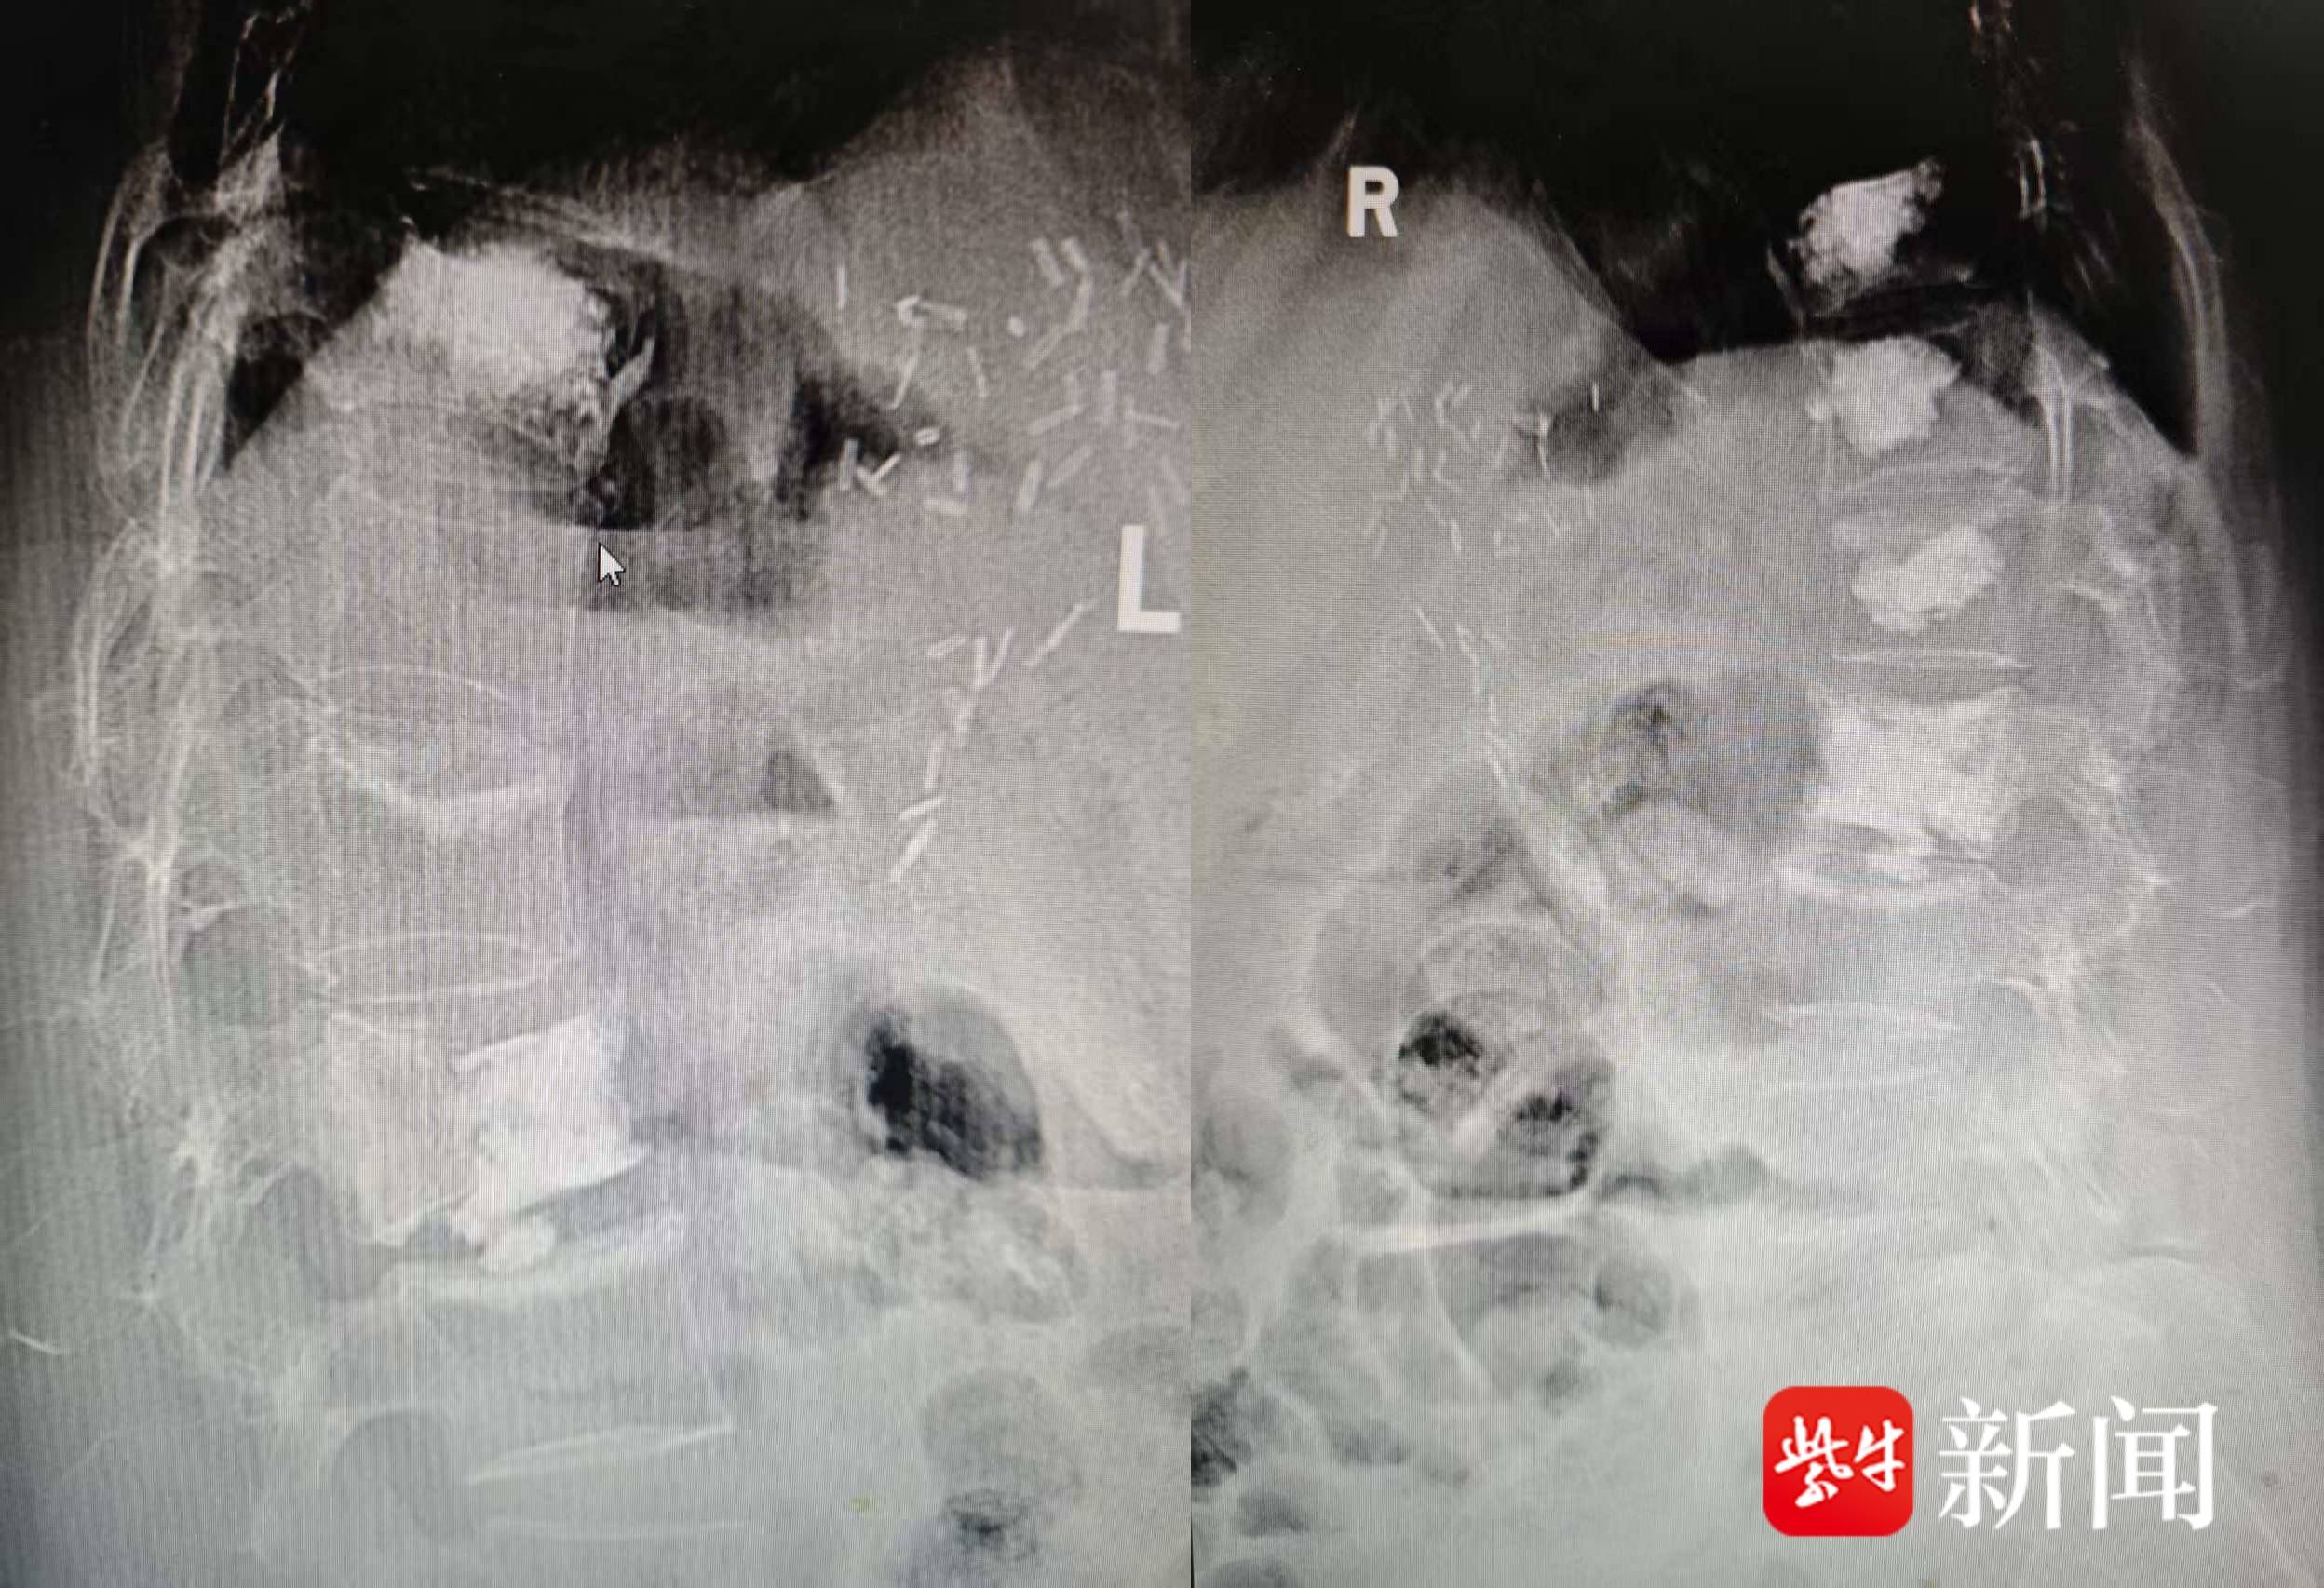

院方介绍,刘女士(化名)约三个月前因肝癌在镇江三院肝科治疗,其间出现腰背痛并持续加重,伴有下肢无力。MRI检查发现其胸12、腰1椎体存在转移灶伴病理性骨折。经骨科主任医师狄东华团队会诊,患者腰背痛已反复两个多月,且曾在外院接受过胸椎椎体成形术,进一步分析MRI发现,其腰2椎体因既往手术骨水泥注入不足,出现了分层断裂,这也是疼痛的重要原因。

影像图

经团队讨论,决定为刘女士实施胸12、腰1及腰2的椎体成形术。手术由尹良东副主任医师主刀,历时一小时顺利完成。